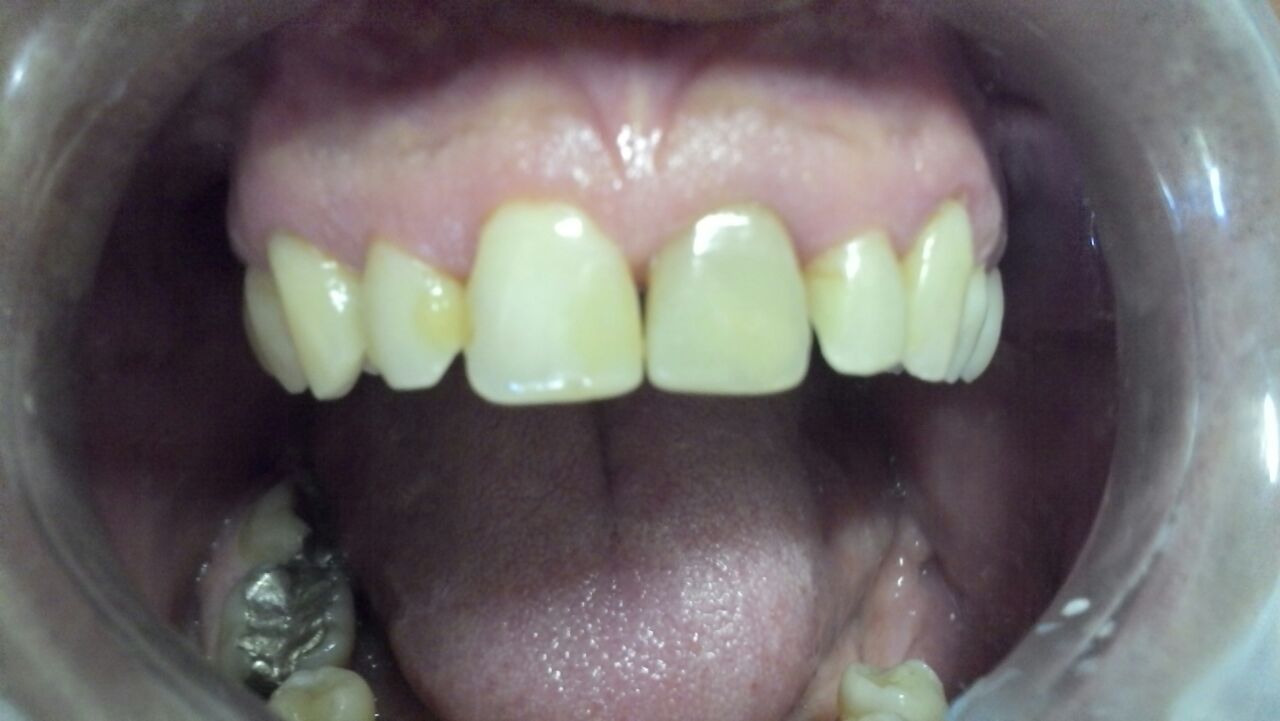

Paciente homem 45 anos. Possuía várias restaurações em resina nos dentes anteriores, já degradadas pelo tempo. Cada uma estava de uma cor diferente.

Além disso o paciente possuía diastemas(espaços) entre os dentes. Os incisivos laterais eram muito pequenos, desproporcionais. As inclinações dos dentes entre si eram incompatíveis e o incisivo central direito estava escurecido por tratamento de canal.

Podemos melhorar.

Realizou-se então raspagem e profilaxia. Depois fez-se o clareamento dentário, o que é fundamental em casos extensos como esse. Ainda para ele que tinha os dentes, cada um de uma cor diferente.

E por fim procedeu-se as facetas em resina composta de canino direito até canino esquerdo.